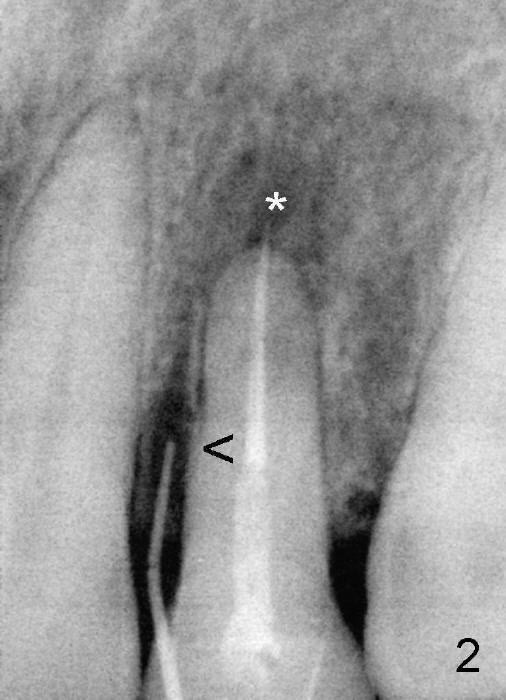

Fig.2: A gutta percha inserted to the buccal fistula (Fig.1 >) shows a mesial defect ( <). *: periapical radiolucency. Fig.3. Immediately post implantation (4x20 mm). Fig.11: Four months postop. Crest bone appears to have mild resorption (arrow).